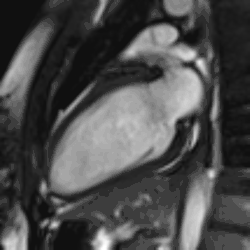

Heart function using cine imaging

Functional and structural information is acquired using bSSFP cine sequences. These are usually retrospectively-gated and have intrinsically high contrast in cardiac imaging due to the relatively high T2:T1 ratio of blood compared to myocardium. Images are typically planned sequentially to achieve the standard cardiac planes used for assessment. Turbulent flow causes dephasing and signal loss allowing valvular disease to be qualitatively appreciated. The left ventricular short axis cines are acquired from base to apex and are used for quantifying end-diastolic and end-systolic volumes, as well as myocardial mass. Tagging sequences excite a grid pattern that deforms with cardiac contraction allowing strain to be assessed.